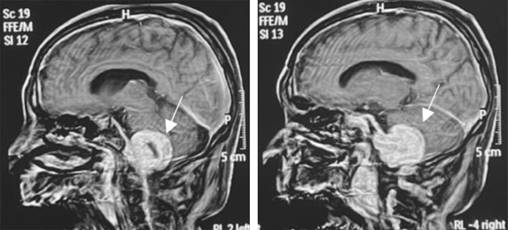

Se realiza resonancia magnética de cráneo debido a la sintomatología antes mencionada; reporta un schwannoma de localización intra y extracraneal (Figuras 1 y 2).

El estudio de elección para diagnosticar los schwannomas es la resonancia magnética, siendo la prueba de mayor definición. En este caso, encontramos afectado el bulbo raquídeo que contiene estructuras como el centro cardiorrespiratorio, los nervios glosofaríngeo y vestibulococlear y el centro de deglución; el efecto de masa explica los síntomas de hipoacusia sensorial ipsilateral y disfagia por la abolición del reflejo de deglución. Otra estructura afectada es el centro cardiorrespiratorio, que al estar siendo comprimido resulta en un estado de acidosis respiratoria crónica.